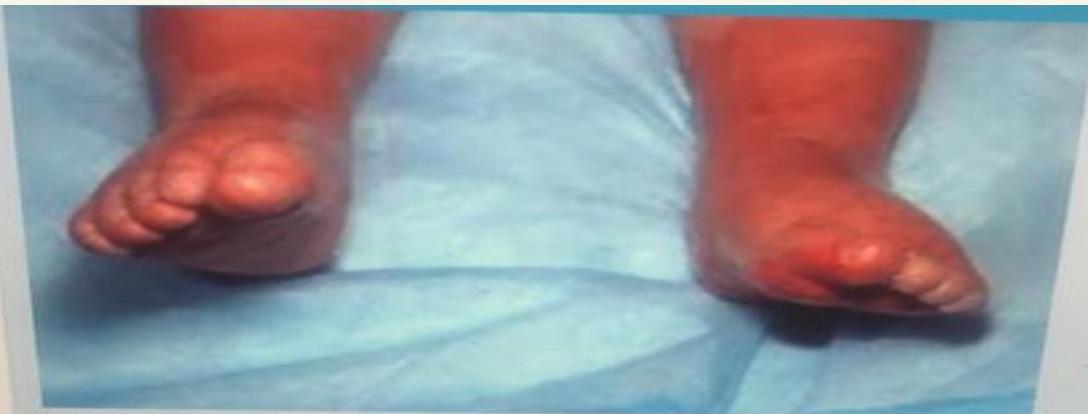

Turner Syndrome (45X0)

webbed neck, edema foot at birth, everything widening.

Neonatal Jaundice Grading

| Grade | Extent of Jaundice |

|---|---|

| 0 | None |

| 1 | Face and neck only |

| 2 | Chest and back |

| 3 | Abdomen below umbilicus to knees |

| 4 | Arms and legs below knees |

| 5 | Hands and Feet |

Grade in the neonate shown? Grade 5.

Management? Check TSB and choose accordingly: exchange transfusion or phototherapy.